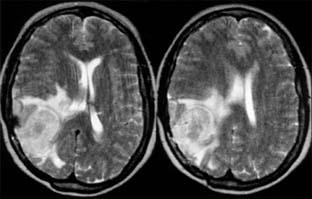

During an acute episode of optic neuritis, MRI shows gadolinium enhancement, increased signal on short tau inversion recovery (STIR) sequences, and sometimes swelling of the affected nerve. Brain MRI will show lesions consistent with demyelination in as many as 25% of patients with isolated optic neuritis (Figure 14-10). This does not establish a diagnosis of multiple sclerosis, though it does indicate a significantly increased risk of subsequent development of clinically definite multiple sclerosis. The value of steroid treatment in delaying the development of multiple sclerosis is greater in patients with abnormal brain MRI at presentation. Thus, brain MRI may be indicated in isolated optic neuritis if more precise information is wanted about the risk of multiple sclerosis and the value of systemic steroid treatment.

Figure 14-10

Figure 14-10: Cerebral hemisphere white matter lesions on MRI associated with acute demyelinative optic neuritis.